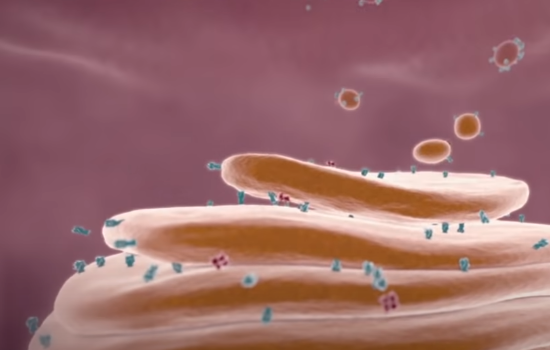

当一位感染者通过打喷嚏,甚至说话聊天时,携带病毒的飞沫就有可能会落在你的嘴,鼻子里,进而进入肺部。

这些飞沫携带着小到人肉眼是不可见的冠状病毒,以至于科学家只能用电子显微镜给它拍照:

病毒身材呈圆形或椭圆形,直径约60-140nm,是一根头发丝的六百分之一。